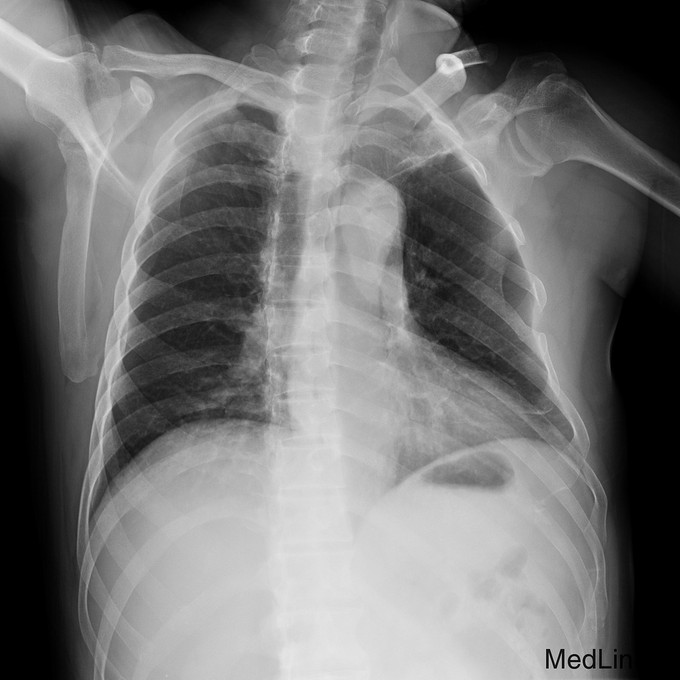

主诉:摔伤后左肩疼痛伴活动受限20天。 病史:患者入院前20天不慎摔伤,左肩不能活动,遂来我院急诊,摄片示左肩锁关节脱位,入院治疗。

完善术前检查和准备后,行左肩锁关节脱位切开复位内固定术,术顺,术后安返病房,内固定使用锁骨钩。

随访示内固定在位,复位位置可。